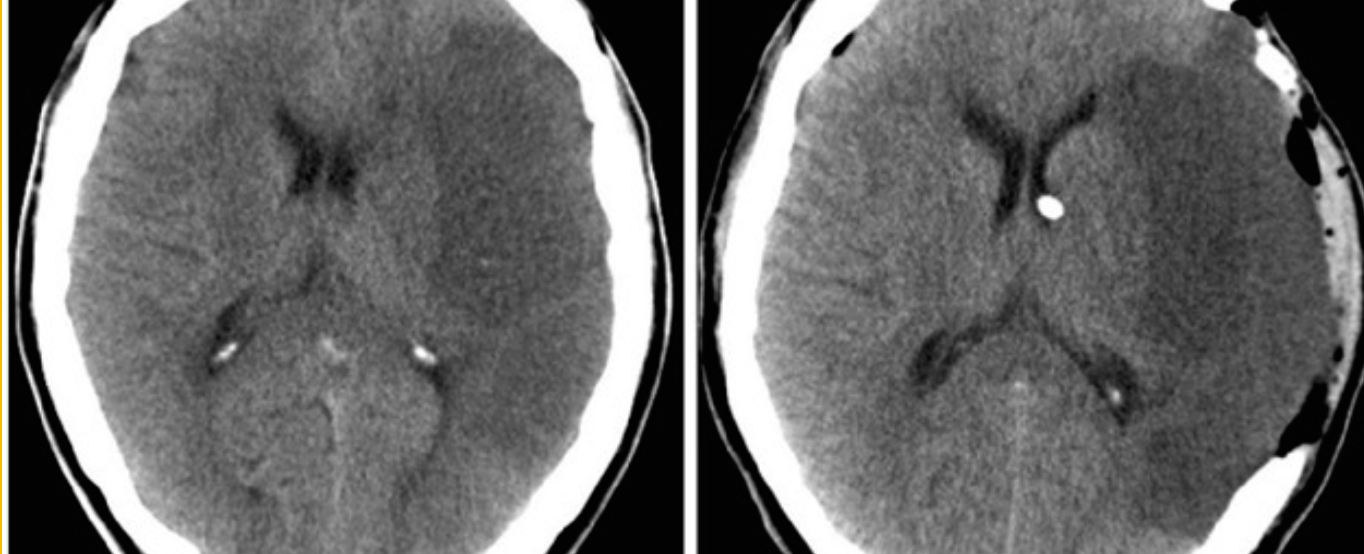

Case 11

-

Describe 2 abnormal findings of the CT?

a. Left hypodense area occupy the left hemisphere (infarction)

b. Left carinotomy mark -

Name vascular territory involved?

a. Middle cerebral artery